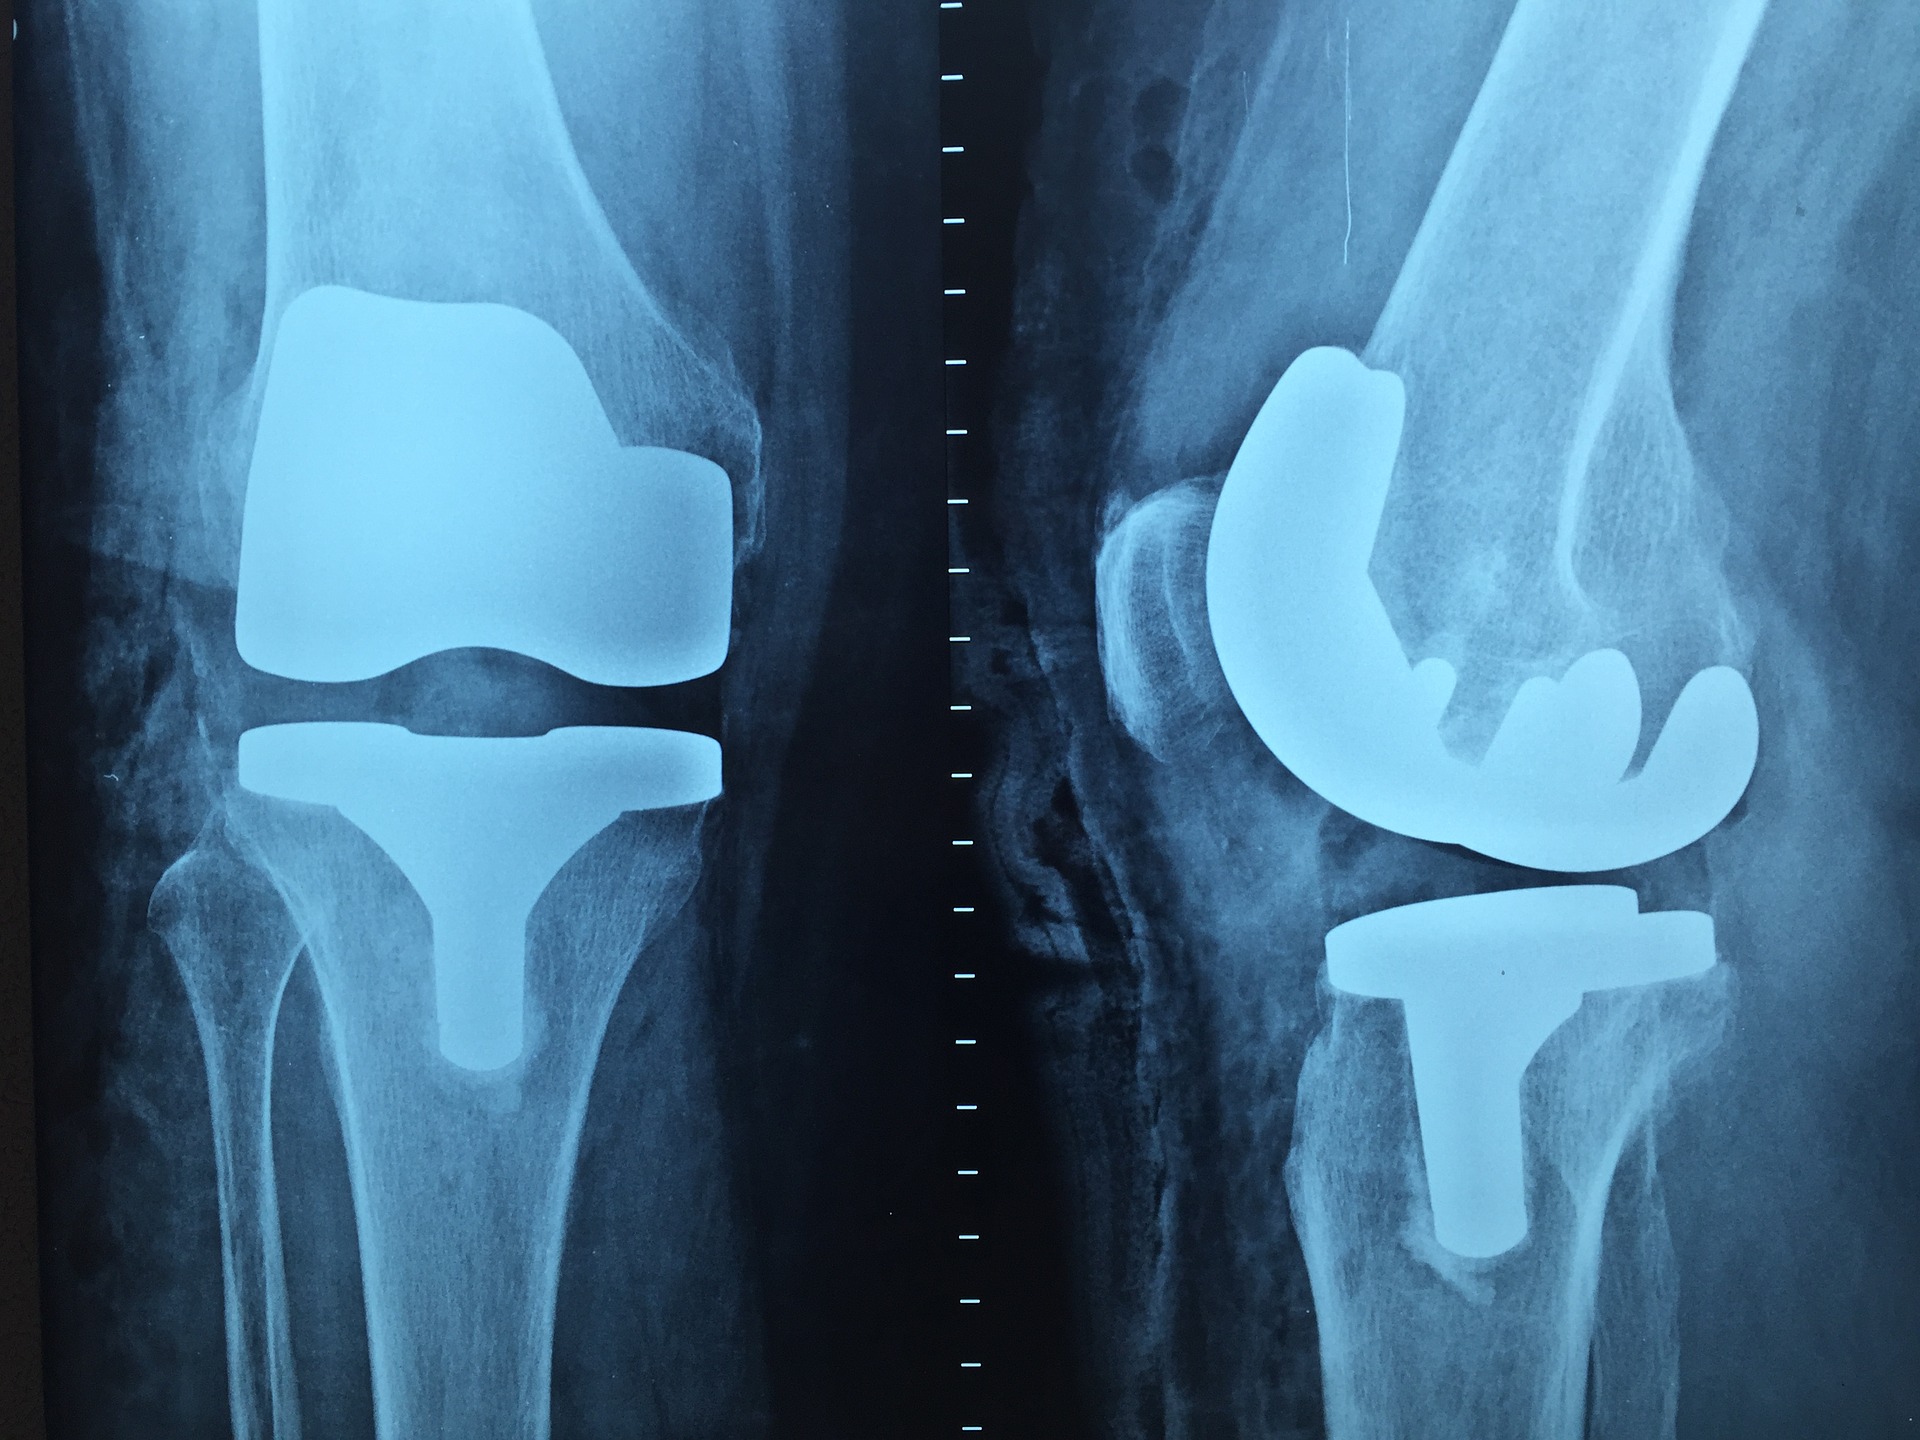

Obecnie bardzo wiele spotyka nas różnych wypadków. Aktywne życie czy uprawianie sportu mogą postawić nas …

Rehabilitacja to dziedzina medycyny, która bardzo szybko się rozwija. Nie wiedzieliśmy kiedyś jak wielki potencjał …

Rehabilitacja to dziedzina medycyny, która bardzo szybko się rozwija. Dawniej nie wiedzieliśmy, jaka moc w …

Rehabilitacja to dziedzina medycyny, która bardzo szybko się rozwija. Nie wiedzieliśmy kiedyś jak wielki potencjał …

Jedną z szybciej rozwijających się dziedzin jest rehabilitacja. Nie wiedzieliśmy kiedyś jak wielki potencjał w …